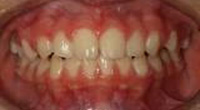

4、開咬(前歯を閉じることができない)

・乳歯列期から治療を開始することを推奨します。

歯の位置は、唇や頬の筋肉(外側からの力)と舌の圧力(内側からの力)のバランスによって決まります。つまり、どこかに発育不全の部分があると、この正常なバランスが崩れて不正咬合を引き起こしてしまうのです。

最近は特に、口をいつもあけている(口呼吸)子どもたちが非常に多くなってきていますが、口呼吸でたえず口を開けていると、舌を正しい位置に収めることができなかったり、唇まわりや頬の筋肉などを正常な状態で使えなかったりして、口周りの筋肉のバランスが崩れてしまいます。

その結果、開咬になり、口呼吸がもっとひどくなる可能性がありますので早い段階での軌道修正をおススメします。